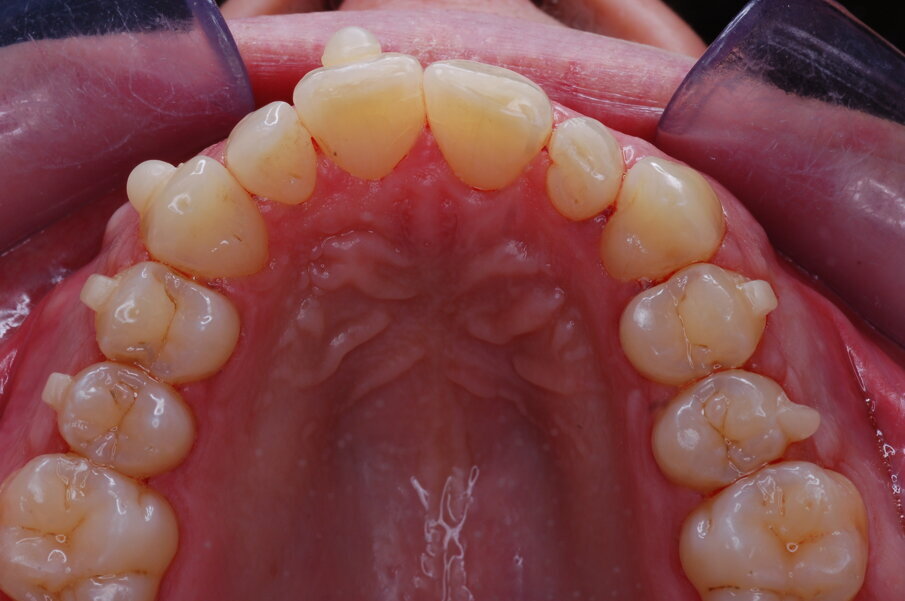

Risultati del trattamento Le fotografie extraorali post-trattamento hanno mostrato il miglioramento dell’estetica del sorriso (Figg. 51-58). È stata ottenuta una solida occlusione bilaterale di Classe I con overjet e overbite normali. Le arcate dentali erano ben allineate e livellate e anche la grave rotazione del secondo premolare mandibolare sinistro è stata corretta solo con gli allineatori. La valutazione cefalometrica post-trattamento (Fig. 59) ha mostrato un miglioramento della posizione anteroposteriore degli incisivi mandibolari (Li-APog: 2,21 mm), pur mantenendo l’altezza facciale (altezza facciale inferiore: 53,12°; asse facciale: 83,96°; Tab. 1). La radiografia panoramica mostrava che la radice dell’incisivo laterale mandibolare destro era stata raddrizzata dall’ausiliario HAT, senza alcun importante riassorbimento radicolare, raggiungendo un buon parallelismo con i denti adiacenti (Fig. 60). I terzi molari mandibolari impattati erano ancora presenti perché il paziente si rifiutava di estrarli.

Figg. 51-58_Fotografie facciali e intraorali post-trattamento.